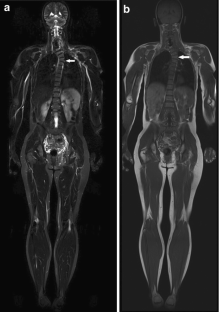

Institutional review board approval and written informed consent were obtained for this prospective HIPAA-compliant study. A total of 247 subjects (141 with NF1, 55 with NF2, 51 with schwannomatosis; 132 women (53.5%); mean age, 41 years, range, 18–97 years) underwent WBMRI using coronal STIR (TR/TE: 4190/111 ms, TI: 150 ms) and T1-weighted images (TR/TE: 454/10 ms), 10-mm slice thickness, imaging time ~40 min. Images were reviewed for the presence of incidental findings, outside of nerve sheath tumors. The presence of scoliosis was recorded and curve morphology was assessed and quantified.

Results

Incidental findings other than scoliosis were recorded in 104/247 (42%) patients, most often affecting the musculoskeletal system (65/247 patients, 26%). We found 16/247 (6.5%) significant incidental findings likely to affect clinical management, including avascular necrosis of bone in eight patients (five with NF2), eight insufficiency fractures, and four non-neurogenic neoplasms (Hodgkin's lymphoma, liposarcoma, dermoid cyst, large uterine myoma requiring excision). Scoliosis was seen in 50/247 patients (20%), including 8/55 with NF2 (15%) and 11/51 with schwannomatosis (22%).